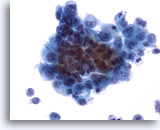

Figure 1

Bronchoalveolar lavage

Low magnification showing an admixture of epithelial cells and macrophages. 20x

Bronchoalveolar lavage

Low magnification showing an admixture of epithelial cells and macrophages. 20x

Figure 1

Bronchoalveolar lavage

Low magnification showing an admixture of epithelial cells and macrophages.

20x